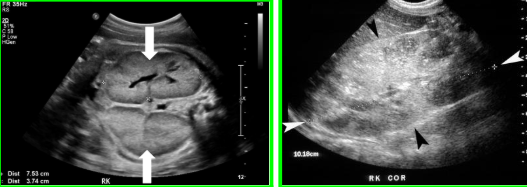

Autosomal Recessive Polycystic Kidney Disease (ARPKD)

Genetic condition, formation of innumerable tiny cysts.

Four kinds: Perinatal, neonatal, infantile, and juvenile.

clinical indications for ARPKD

Portal hypertension (in severe cases), Renal insufficiency - shown via elevated BUN/Creatinine - decreased GFR.

How is ARPKD usually diagnosed

Often during ultrasounds in pregnancy - enlarged hyperechoic kidneys, oligohydramnios, and pulmonary hypoplasia.

Treatment options for ARPKD

If prolonged survival (past birth) - kidney/liver transplant.

prognosis for ARPKD

Severity/progression vary. Often poor, due to lack of fluid and lung development. With prolonged survival kidney/liver transplant may help.

Radiological images description for ARPKD

Enlarged hyperechoic kidneys. May see hepatic fibrosis and splenomegaly in severe cases (with prolonged survival).

ARPKD images